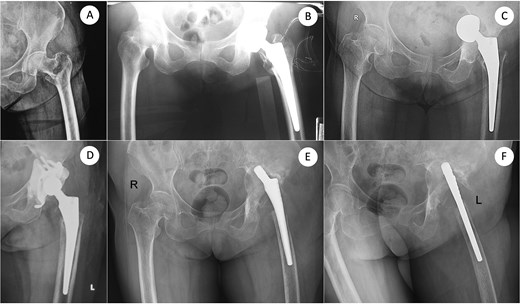

A 73-year-old woman presented with severe bone loss of the left proximal femur and extensive acetabular deficiency with pelvic discontinuity (Fig. 1). Initial treatment in 2017 for a displaced femoral neck fracture was bipolar hemiarthroplasty (Fig. 2A and B). After a new injury in 2019, an acetabular fracture with intrapelvic migration of the bipolar head occurred (Fig. 2C), leading to conversion to total hip arthroplasty with a revision acetabular component supported by a cup–cage (“trap”) construct (Fig. 2D). In 2023, PJI developed with loosening of both components; the acetabular component was explanted and a central pedicled vastus lateralis flap transposed to manage dead space (Fig. 2E and F). In May 2024, the femoral component was removed (Fig. 3A). CT confirmed mixed cavitary–segmental acetabular defects and marked metaphyseal loss of the proximal femur (Fig. 3B). After normalization of inflammatory markers and soft-tissue healing, salvage re-revision THA was performed. Acetabular reconstruction used a 52-mm porous shell–cage; two 45-mm tongues engaged host ilium and ischium, and cavitary defects were filled with antibiotic-loaded polymethylmethacrylate. Fixation comprised three intra-shell screws, four rim screws, and two tongue screws (Fig. 3C). On the femoral side, 2 cm of compromised proximal femur was resected to bleeding bone; the canal was reamed to 15 mm for circumferential endosteal contact. A modular tapered, fluted stem (14 × 260 mm) achieved distal fixation, supplemented by two distal interlocking screws; prophylactic cerclage mitigated iatrogenic fracture risk (Fig. 3C). Postoperatively, weight bearing advanced as tolerated. Serial AP pelvis radiographs showed a stable cup–cage without migration or progressive radiolucency and a well-seated stem without subsidence. At 10 months there were no complications, no infection or dislocation, and the patient ambulated with a cane; radiographs remained stable (Fig. 2D).

From femoral neck fracture and bipolar hemiarthroplasty to acetabular perforation, conversion THA, and acetabular component removal. (A) Anteroposterior (AP) pelvis radiograph demonstrating a displaced femoral neck fracture. (B) Immediate postoperative AP view after bipolar hemiarthroplasty using a standard femoral stem. (C) Subsequent acetabular perforation with intrapelvic migration of the bipolar head. (D) Conversion to total hip arthroplasty with an acetabular component supported by a cup–cage construct. (E, F) Same sitting: AP and cross-table lateral views obtained at the time of acetabular component explantation, delineating extensive acetabular bone loss. AP, anteroposterior.

Definitive salvage re-revision THA: Defect assessment after femoral explant (AP and 3D-CT) and final reconstruction. (A) AP pelvis after removal of the femoral component showing severe acetabular and proximal femoral bone defects. (B) Three-dimensional computed-tomography (3D-CT) reconstruction corresponding to (A), confirming mixed cavitary–segmental acetabular defects. (C) Immediate postoperative AP radiograph after salvage re-revision total hip arthroplasty using a cup–cage acetabular reconstruction and a 260-mm modular tapered femoral stem secured with two distal interlocking screws. (D) AP X-ray taken 10 months after re-revision. AP, anteroposterior; 3D-CT, three-dimensional computed tomography; THA, total hip arthroplasty.